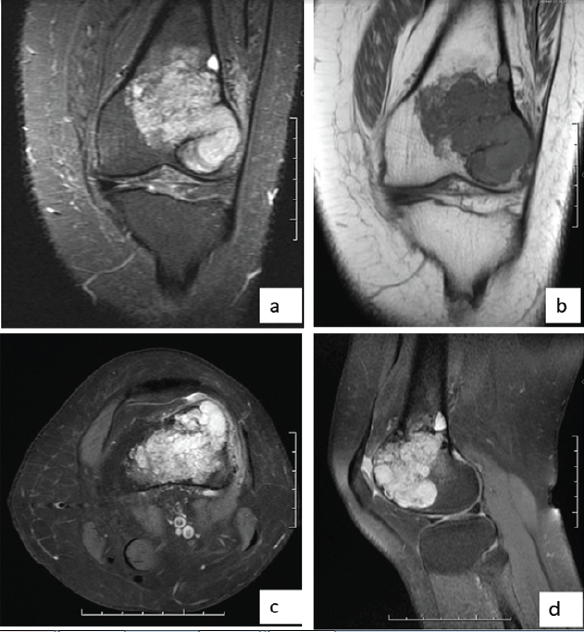

The patient is a 44-year-old female who presented with a progressively enlarging, painful swelling in the left distal femur. The swelling had been present for several months and was associated with localized pain that worsened over time. Radiographic imaging (Fig. 1) revealed an osteolytic lesion in the distal femur with ill-defined margins and a narrow zone of transition, suggestive of a GCT (Campanacci grade 2). Magnetic resonance imaging (MRI) of the lesion (Fig. 2) was done which revealed a well-defined lesion in epi-metaphyseal lesion measuring 64 × 52 × 38 mm on the left side of distal femur, associated with a large soft tissue mass, with no intra-articular extension.

Figure 2: Magnetic resonance images. (a) T2w coronal image, (b) T1w coronal image, (c) T2w axial image, (d) T2w sagittal image showing lesion in the distal aspect of left femur.